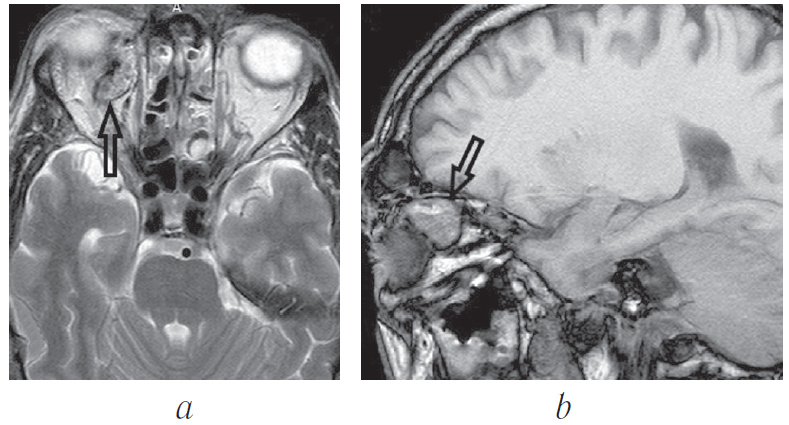

Через 1 год после операции пациент (рис. 23) жалоб не предъявляет. Выполнена контрольная магнитно-резонансная томография головы. Данных за рецидив образования глазницы, головного мозга — нет (рис. 24).

Рис. 24. Больной Г., 68 лет. Магнитно-резонансная томограмма Т1 ВИ. До (a, c) и после (b, d) операции. 1 — новообразование. a, c — парасагитальная, b, d — корональная проекции

Fig. 24. Magnetic resonance imaging T1 WI. Images before (a, c) and after (b, d) surgery. 1 – tumor. a, c – parasagittal, b, d – coronal projections